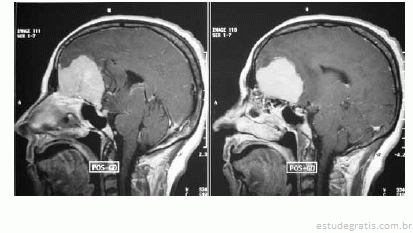

Considerando a figura acima, que mostra o resultado do exame de imagem de um paciente, julgue os itens seguintes.

Fatores hormonais estão envolvidos no desenvolvimento da doença do referido paciente devido à presença de receptores de hormônios sexuais nas células neoplásicas.Comentários